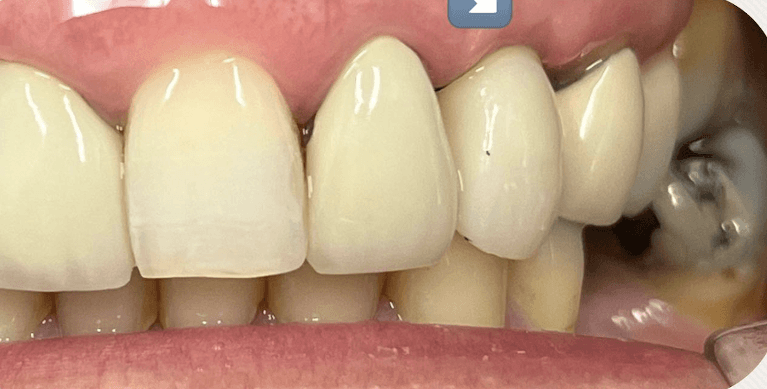

Smiles are always in fashion because the prettiest thing you can wear is a smile (maybe mask for a time being ) Before and after pictures of 4 porcelain veneers.

Smiles are always in fashion because the prettiest thing you can wear is a smile (maybe mask nowadays) Before and after pictures of yesterday’s case. Slight gum bleeding was from flossing..no biggie